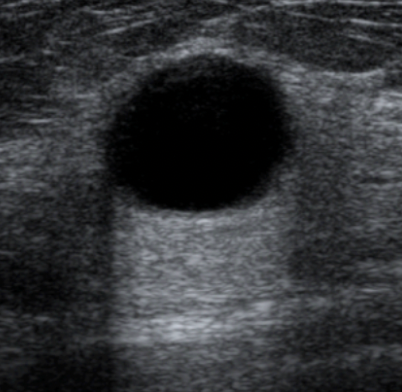

Well defined rounded mass with black, anechoic fluid centre

= cystic mass